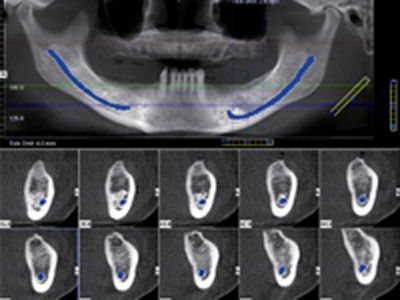

Planung von Implantaten

Die hochauflösenden Bilder zeigen

vollständige dreidimensionale Ansichten kritischer

anatomischer Strukturen. Dies ermöglicht die exakte

Analyse der Knochenstrukturen für die optimale Implantatplatzierung

und -versorgung.

Dazu gehört die Auswahl des am besten geeigneten Implantats

nach Typ, Größe und Position schon vor dem chirurgischen

Eingriff.